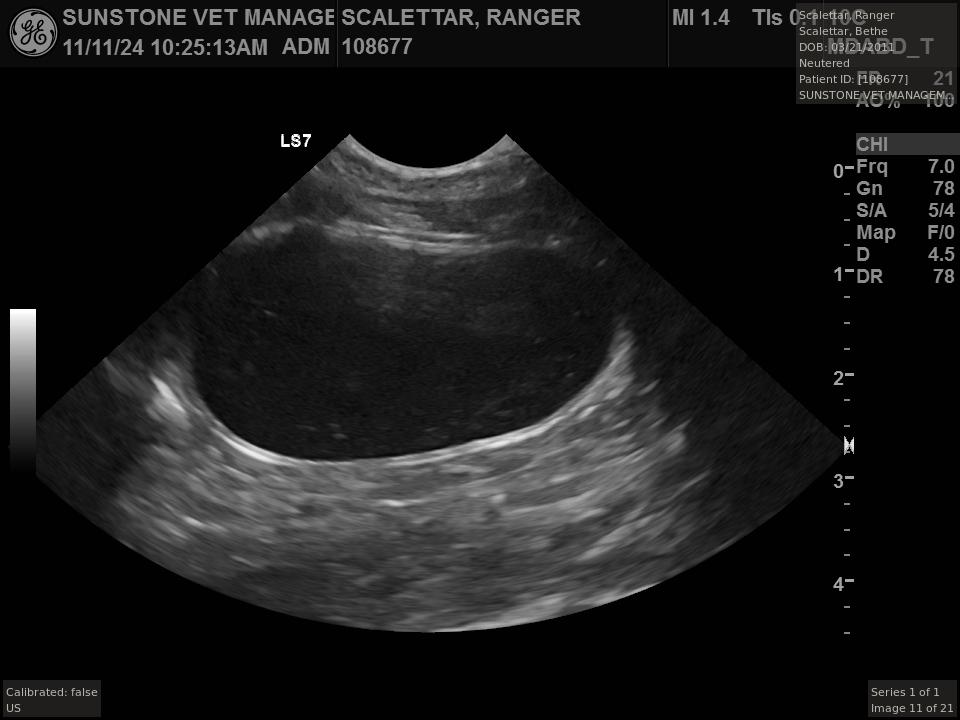

The veterinarian generated a series of images showing different organs and substructures by

changing the position and orientation of the ultrasound transducer. The images were collected

in a defined order, which is repeated from patient to patient, ensuring that nothing is missed. In

Ranger's case, the sonographer collected about twenty images during an examination that

lasted about fifteen minutes.

The sonographer stated that Ranger's ultrasound images were largely normal for an older cat. In particular, they show changes in the kidneys that are commonly noted in geriatric cats and that reflect a risk for the development of chronic kidney disease. However, the images did not show any significant abnormalities in Ranger's stomach, intestines, and associated lymph nodes. Nonetheless, the results did not rule out recurrence of Ranger's small cell lymphoma.